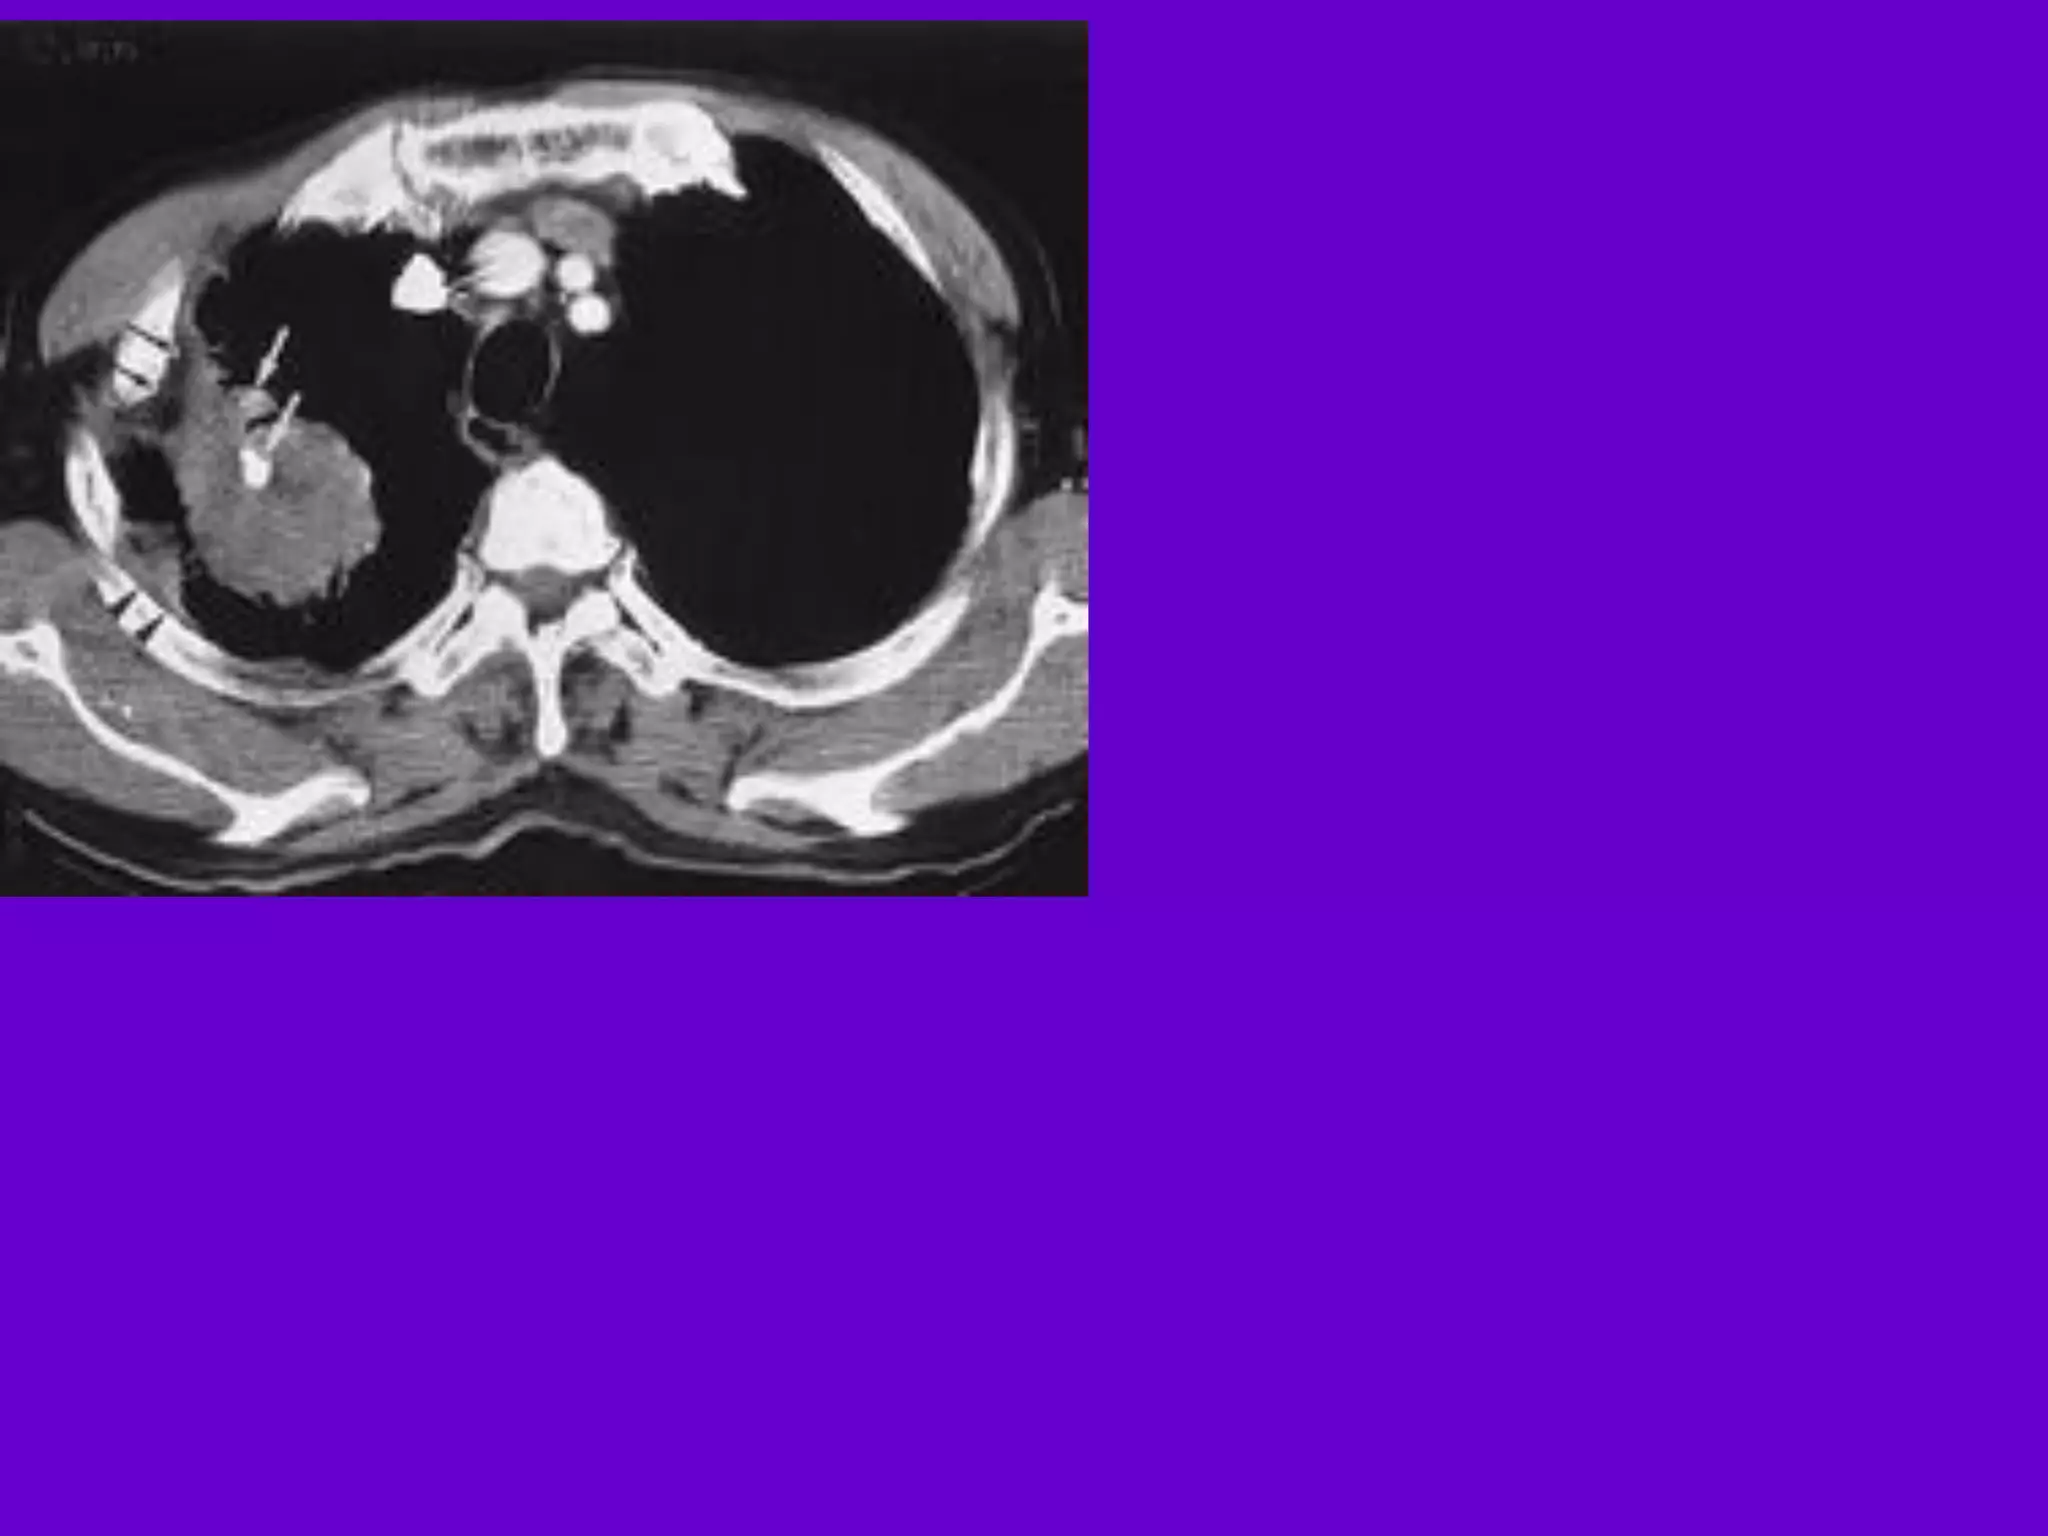

Pulmonary TB :

Lobar Pneumonia

􀂄

CT is superior than plain CXR in picking

up the

consolidation, atelectasis and the hilar LN

thereby

making the diagnosis easy.

􀂄 MRI reveals some of these changes,

however, CT is

the diagnostic modality of choice in such

cases.

Bronchopneumonia

On CT it is usually B/L and widespread,

not always

symmetrical involvement of lungs.

Hilar and Mediastinal

Lymphadenopathy

CT and MRI depict the hilar and

mediastinal LN

equally well.

􀂄 Calcification in the nodes is however

better seen on

CT.

􀂄 Necrosis is seen as focal areas of low

attenuation on

a CECT.

􀂄 On MRI focal necrosis is seen as areas

of increased

signal intensity on T2W images.